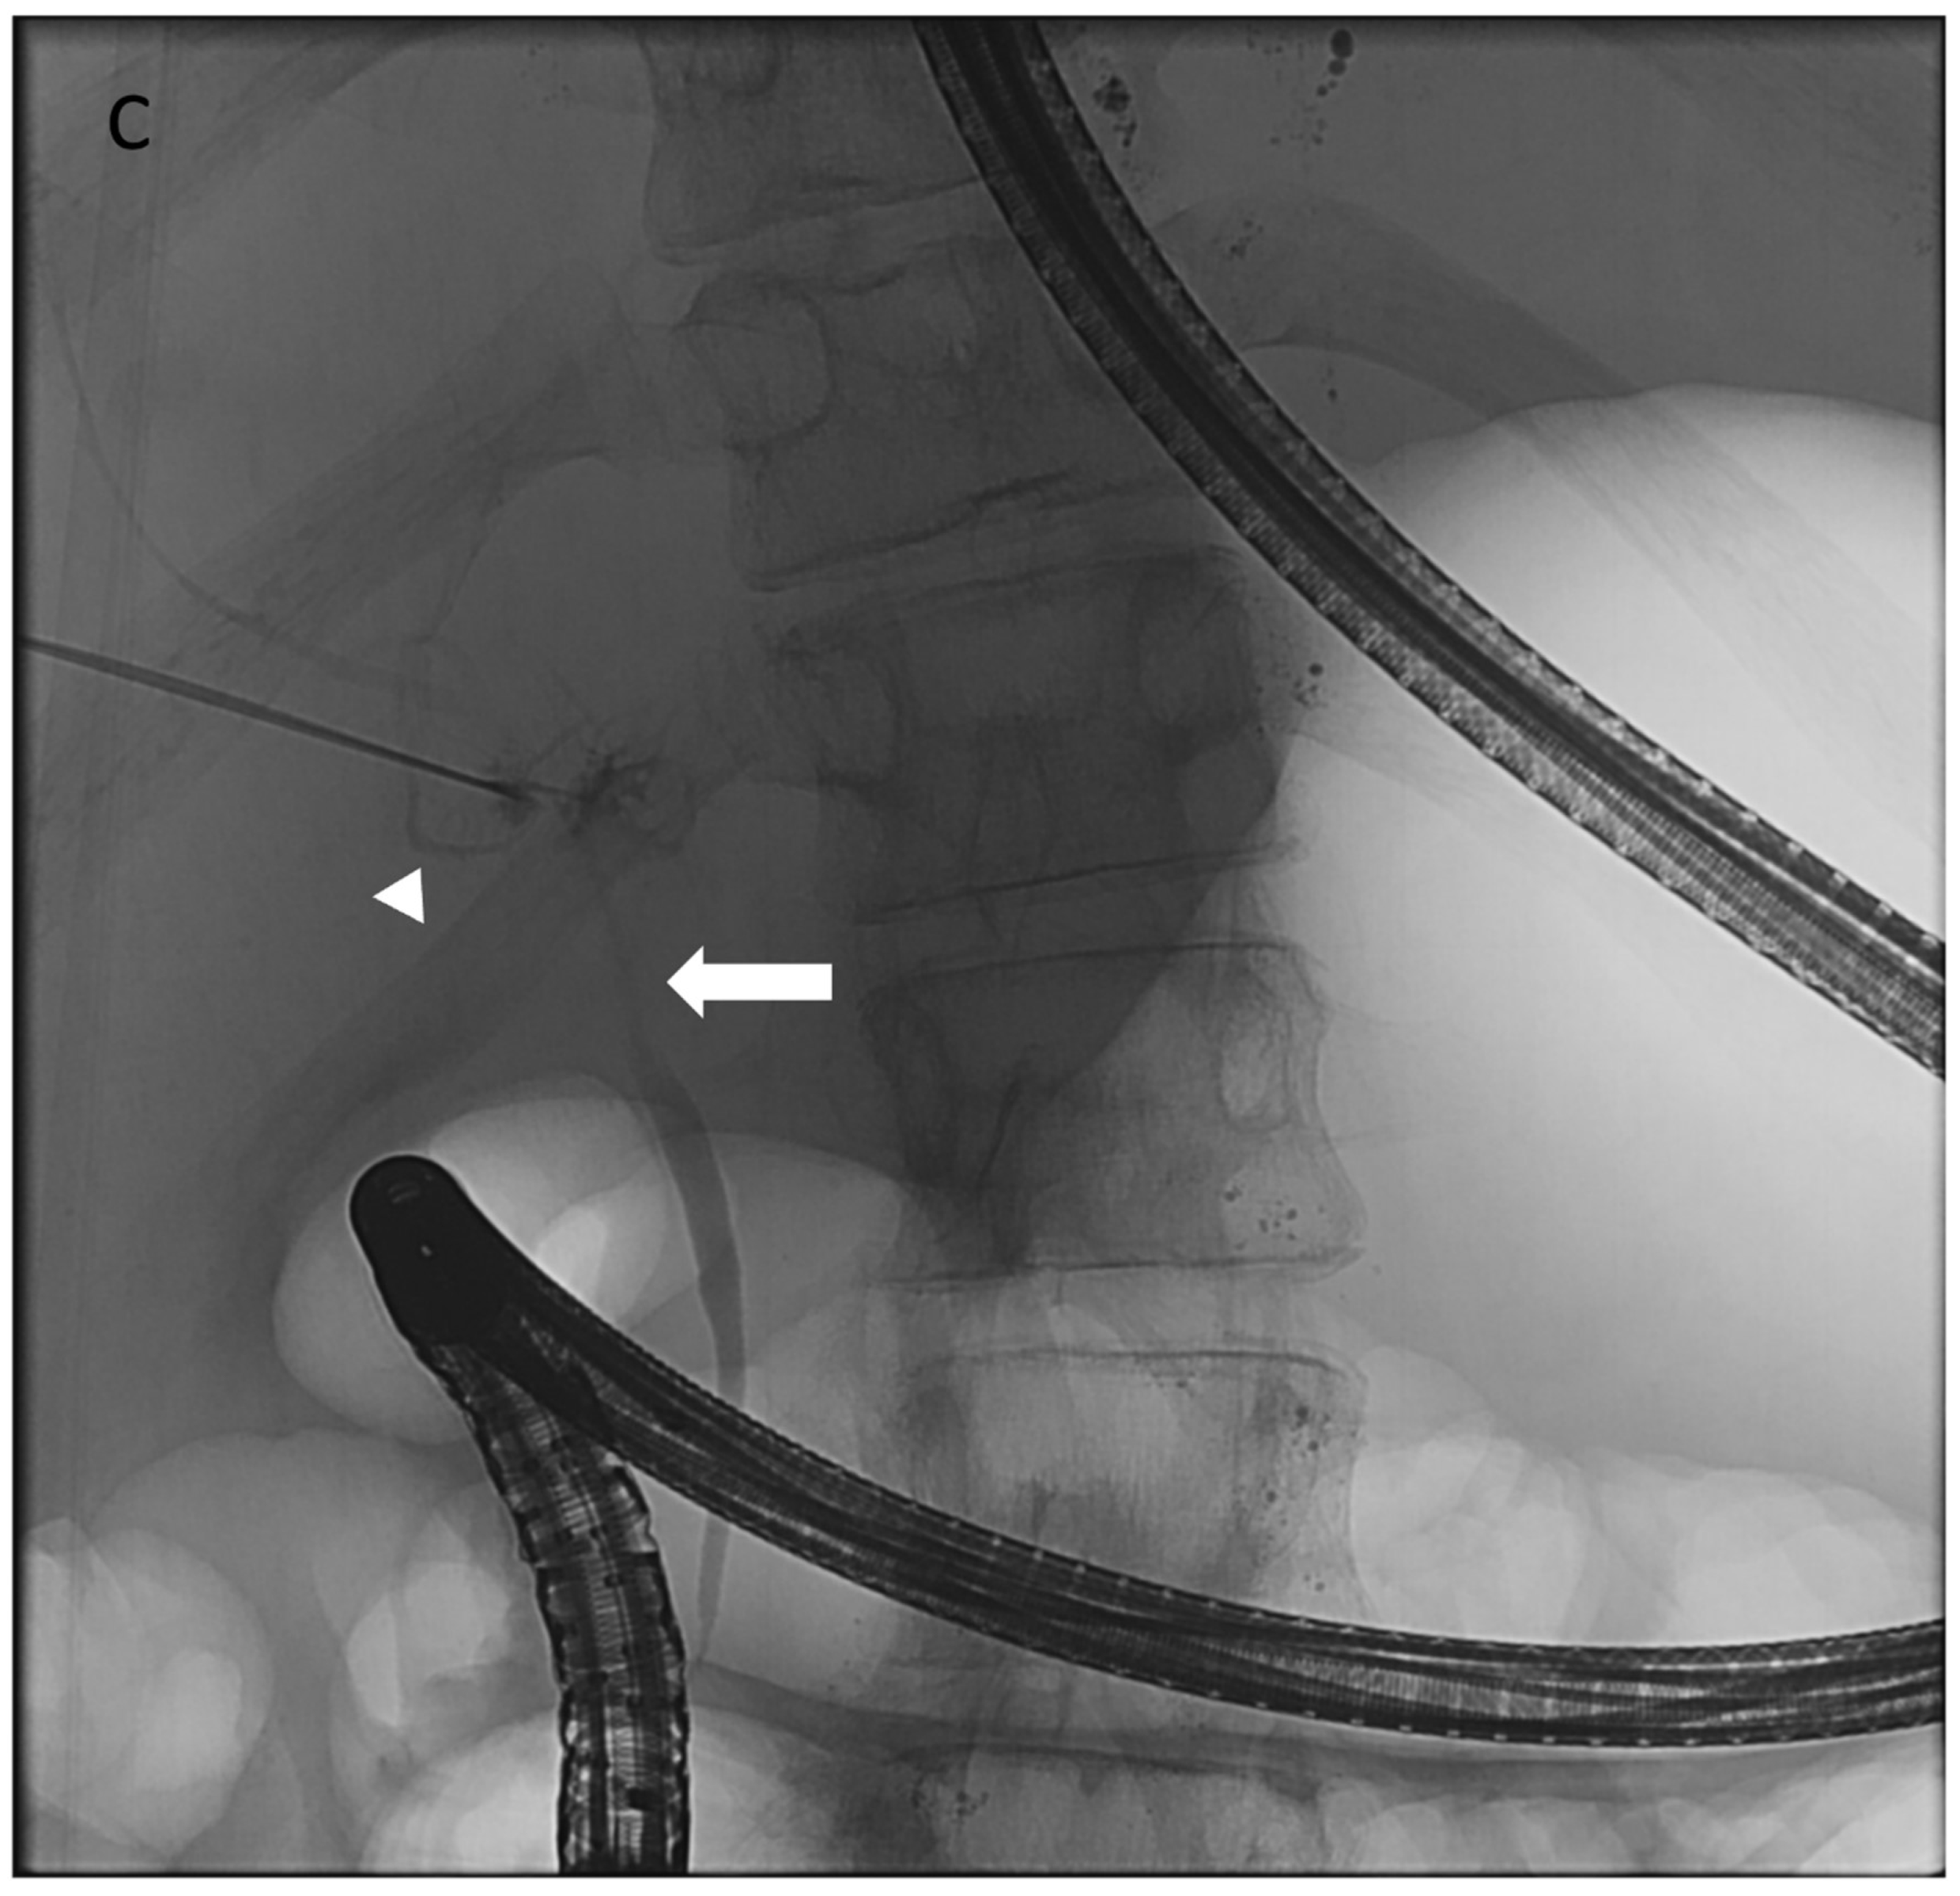

Figure 12. A 16-year-old girl with somatic KRAS mutation and protein-losing enteropathy. (A) A conventional fluoroscopic hepatic lymphangiogram showed an abnormal hepatico-duodenal connection (black arrowhead). (B) Endoscopic view confirmed leakage of hepatic lymph into duodenal lumen upon injection of methylene blue dye using the needle positioned at intrahepatic lymphatic channel. (C) Spot fluoroscopic image showed injection of 25% nBCA/lipiodol mixture using the needle located at right-sided intrahepatic lymphatic channels. (D) Spot fluoroscopic image after injection of glue mixture showed occlusion of hepatico-duodenal lymphatic connection (black arrow). However, the therapeutic effect is short-lived and the PLE recurred within 1 week.

The technical procedure is similar to that of performing an intrahepatic lymphangiogram. Using ultrasound and fluoroscopic guidance, the intrahepatic lymphatics are accessed with 22G or 25G needles. Water-soluble contrast is injected to localize the leakage point or abnormal lymphatic network. In some institutions, additional injection of methylene blue is performed under concomitant upper endoscopy to visualize the abnormal perfusion/leaks, as well as to exclude any connections or contamination of the biliary system [78]. When these networks are identified, they are subsequently embolized with a 25% n-BCA glue/lipidol mixture (Figure 12). Visualization of the embolization often results in glue being seen entering the duodenal lumen through endoscopy and fluoroscopy, confirming occlusion of the abnormal fistulae.

Although generally safe, PTLE adverse events may include glue migration to adjacent vessels/ducts (venous, arterial, and biliary systems) and duodenal bleeding [73]. Care should be taken to avoid transgressing the portal vein during initial access of periportal hepatic lymphatic channels. Duodenal bleeding is likely due to the caustic effect of the embolic glue on the intestinal mucosa, which may be related to the type of glue used. Ethiodized oil was implicated in duodenal bleeding, whereas nBCA glue showed no such effect [77]. However, Maleux et al. reported a case of duodenal bleeding with nBCA. The exact mechanism remains unclear [73].